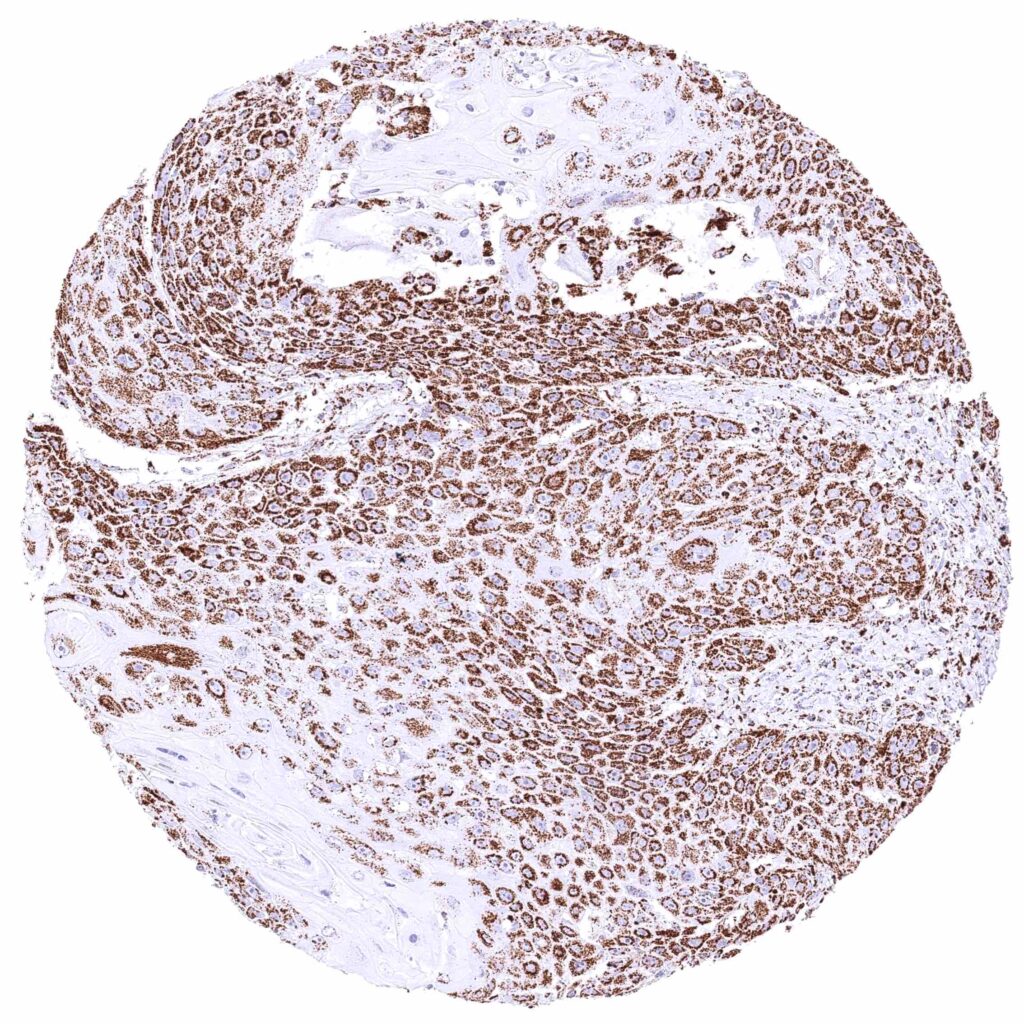

Uterus, cervix – Squamous cell carcinoma with moderate to strong cytoplasmic ATP5J staining of tumor cells.